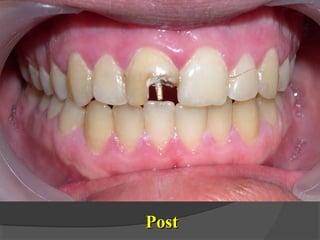

PostPost